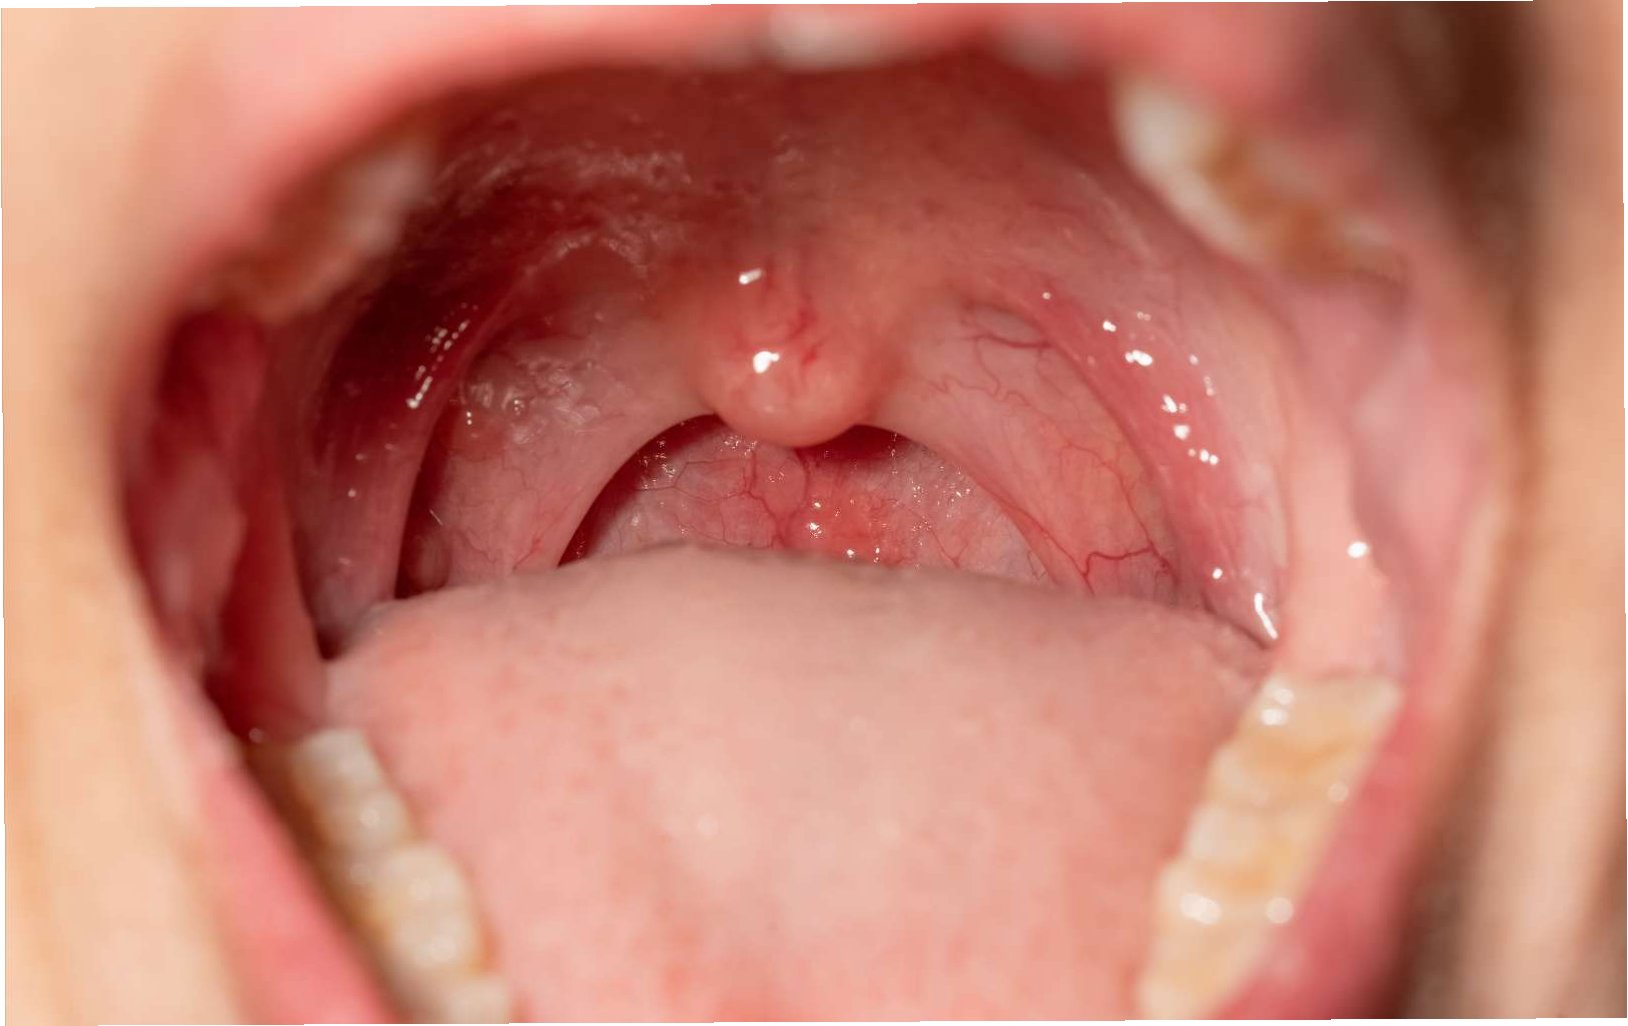

구강암 조기 발견의 중요성

구강암은 조기에 발견될 경우, 치료 성공률이 높습니다. 따라서 정기적인 자가 검진과 치과 검진을 통해 구강 건강 상태를 지속적으로 확인하는 것이 중요합니다. 구강 내 궤양, 덩어리, 통증, 출혈 등 이상 증상이 나타나면 즉시 의료 전문가와 상담해야 합니다. 조기 발견은 구강암 치료의 핵심이며, 건강한 삶을 되찾는 데 중요한 역할을 합니다. 정기적인 검진은 당신의 건강을 지키는 가장 확실한 방법입니다.